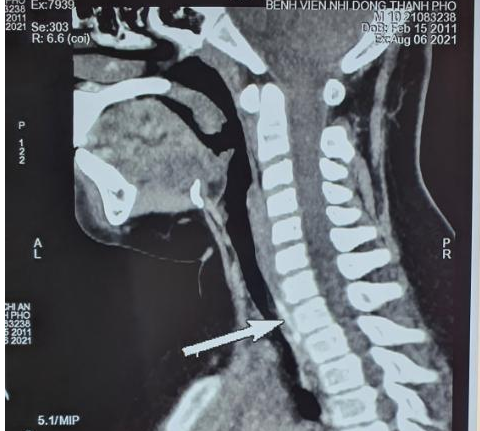

hõ xuong vit -1

Cấp cứu một trẻ hóc dị vật đường thở là đoạn kẽm nhung dài 2cm